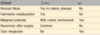

Campylobacter spp.:

geography

transmision

epidemiology

GI site

reservoir

symptoms

complications

high income countries

poultry, milk, contaminated water, other foods - food poisoning

sporadic__, children, travelers

colon

farm animals

water/bloody diarrhea- (travelers diarrhea)

reactive arthritis (pt w/ HLA-B27), guillain-barre syndrome, erythema nodosom